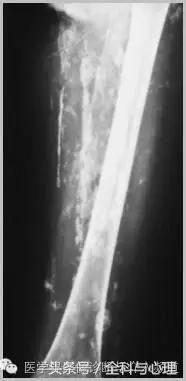

二 、与代谢有关的钙化

1、营养不良性钙化:由组织损伤或退变造成的钙化,没有相关的代谢障碍。

软组织钙化与骨化,软组织钙化和骨质增生

血肿机化